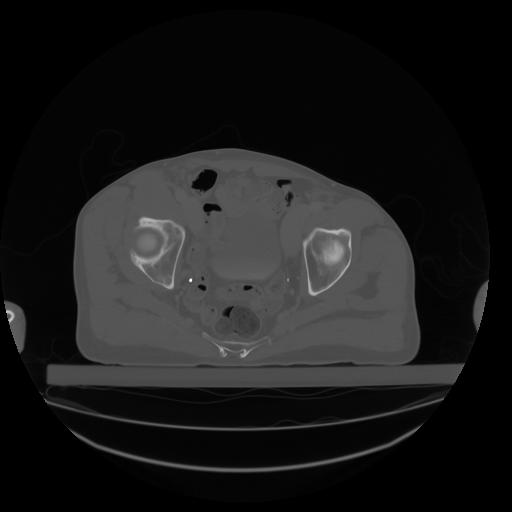

27 CUERPO,CE,Axial,3.0,CUERPO,,